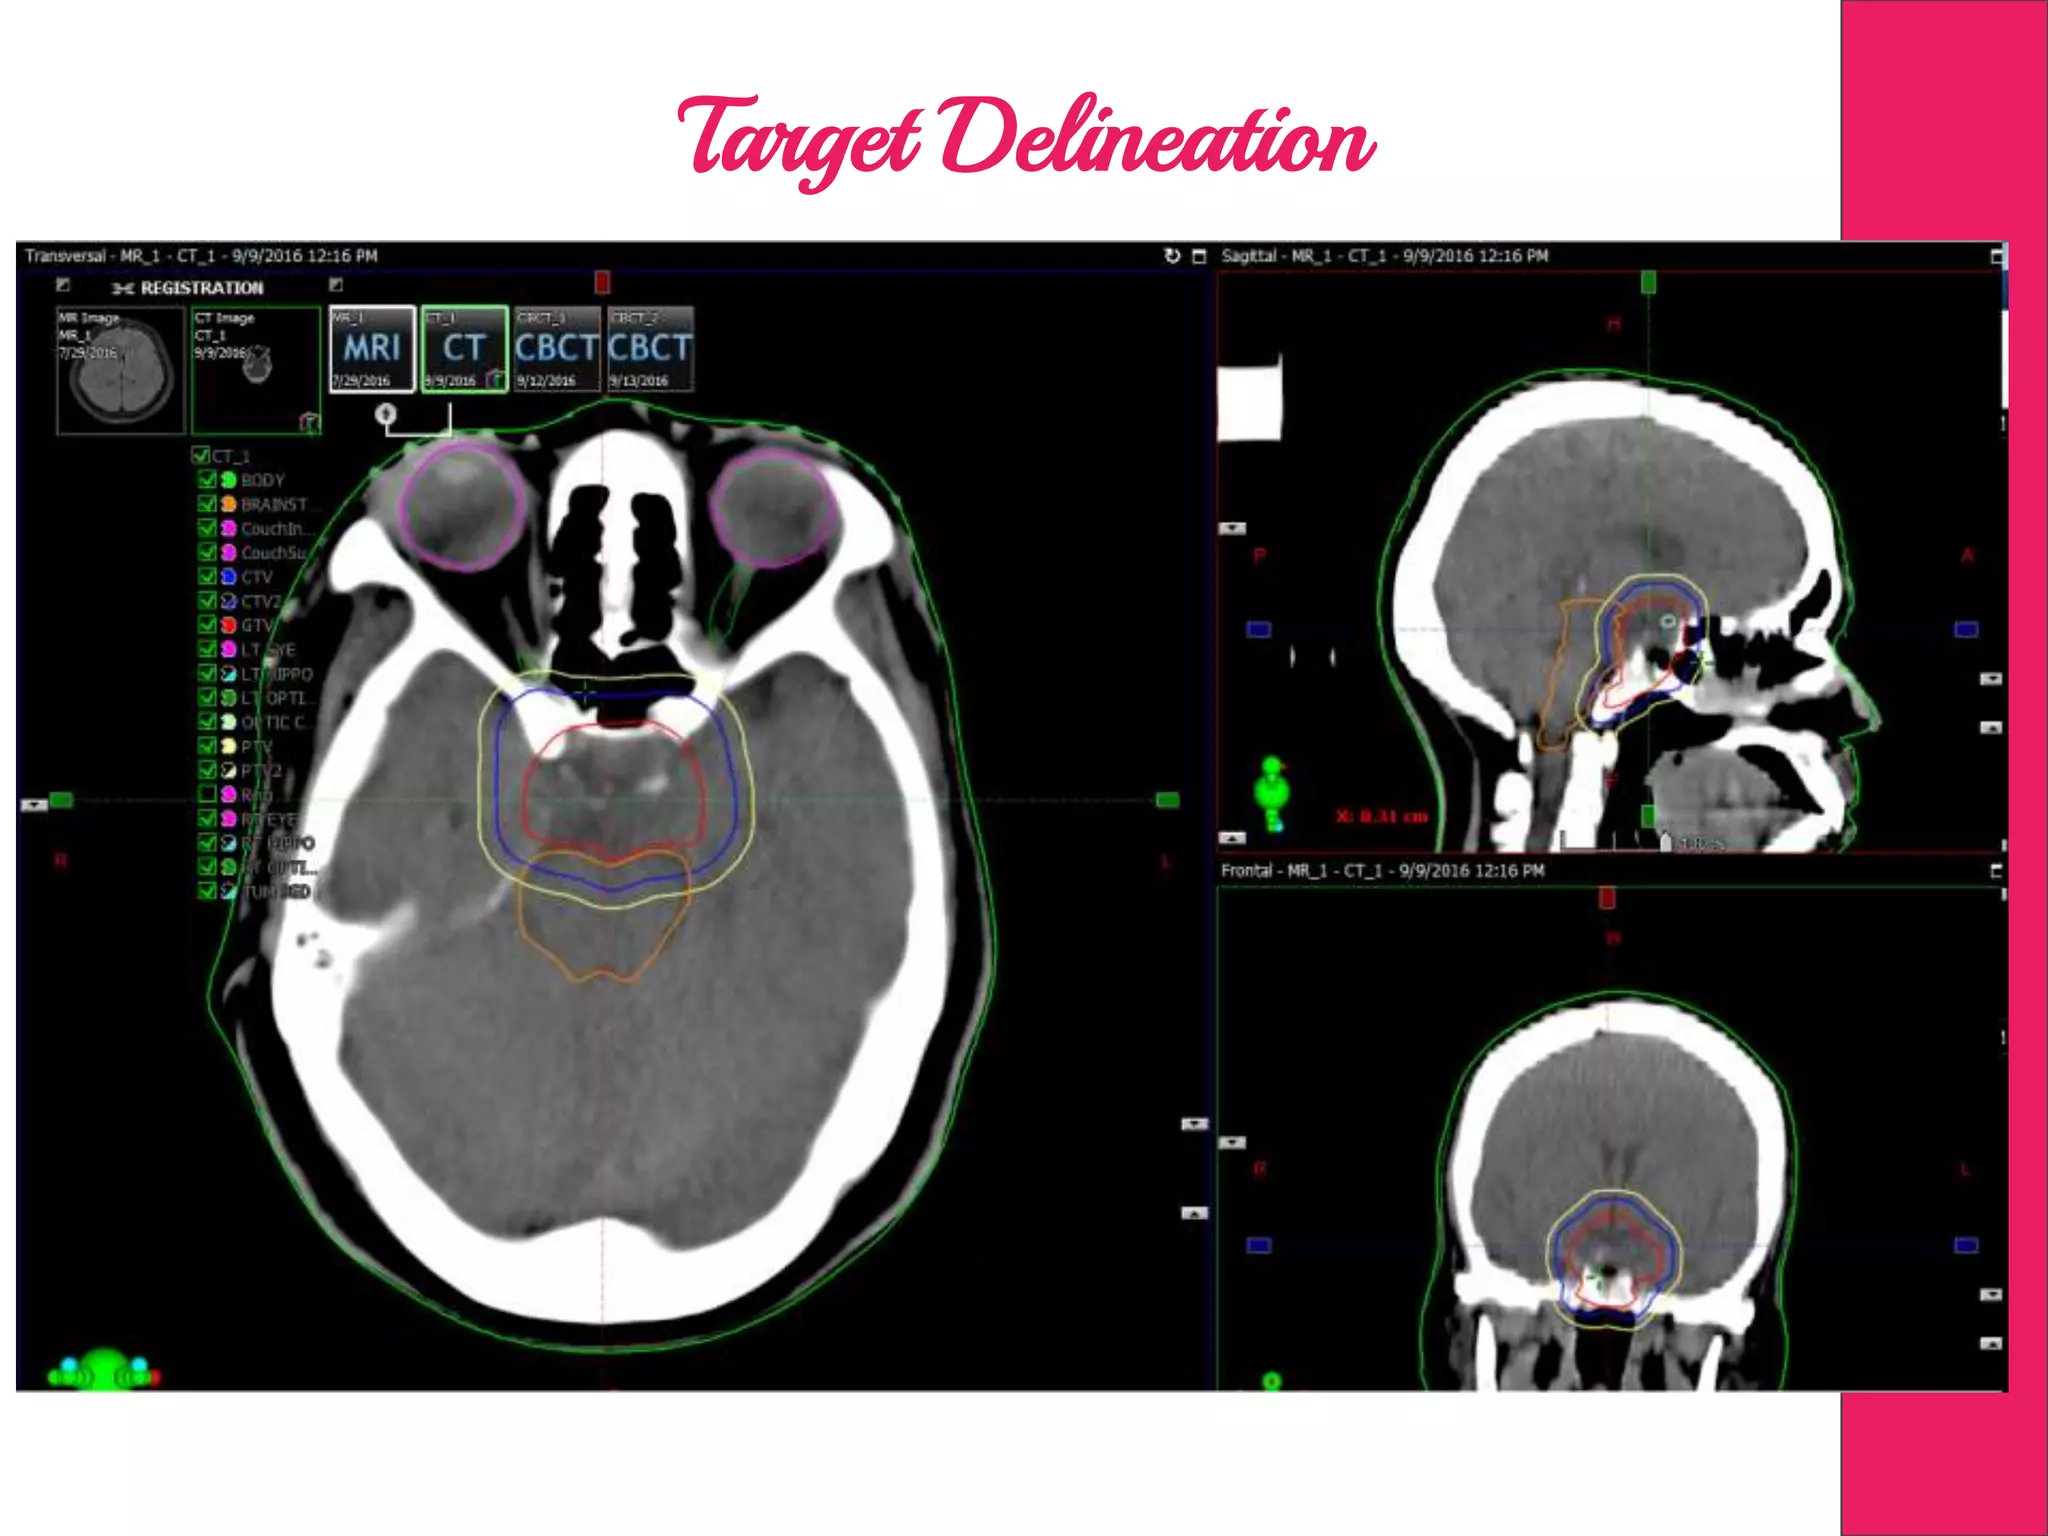

Image Fusion

Target Delineation

MR, PET, DSA &

4DCT

Steps Involved inRadiotherapy Positioning of Patient Imaging in CT Treatment Planning Image Fusion Target Delineation MR, PET, DSA & 4DCT Plan EvaluationDosimetry Verification Image Guidance Treatment Delivery Patient